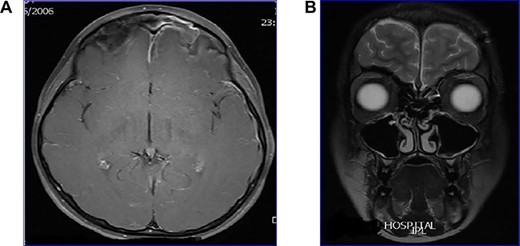

Case 4: frontal lobe abscess

Young man referred as a case of frontal lobe abscess as a complication of untreated frontal sinusitis. The patient presented with fever, headache and changes in personality and mood. Coronal MRI brain (Fig. 4A) showed a large frontal lobe abscess and an inflamed frontal sinusitis as in Fig. 4B. the patient was managed with a combination of intravenous antibiotics, endoscopic frontal drainage and frontal craniotomy to drain the frontal abscess by the neurosurgery team. Patient tolerated the procedures well with no complications as shown in postoperative CT brain (Fig. 4C).

(A) Preoperation coronal MRI brain with large frontal lobe abscess, (B) preoperation sagittal MRI of frontal lobe abscess extending from inflamed frontal sinus and (C) post drainage CT brain showing complete resolution of the frontal abscess.